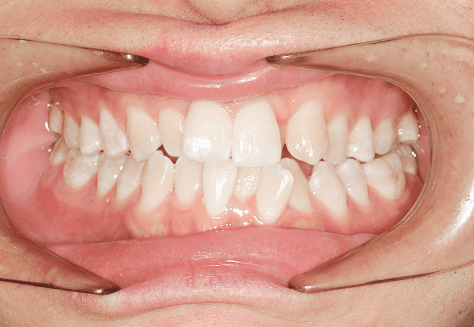

M.U

治療前

治療後

主訴

下の歯が特にガタガタなのが気になる。上の前歯が1本反対になっている。

診断

下顎前突・叢生・反対咬合

年齢/性別

20代/男性

抜歯部位

非抜歯

使用装置

上下インビザライン(PBM使用)

保定装置

ビベラリテーナー

料金

初回資料採得・・・・・・・30,000円

診断料・・・・・・・・・・33,000円

動的治療終了時資料採得・・5,500円 -

基本料金

950,000円

診察料金

5,500円×16回

治療期間

1年7カ月